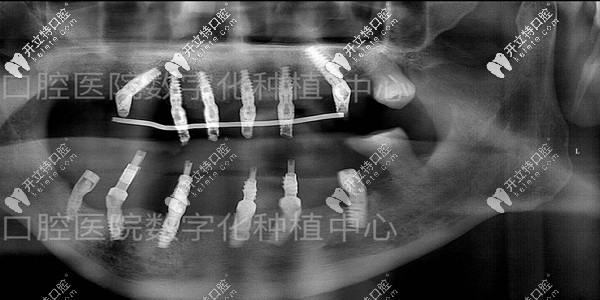

種牙后的拍片

種牙后的口腔檢查